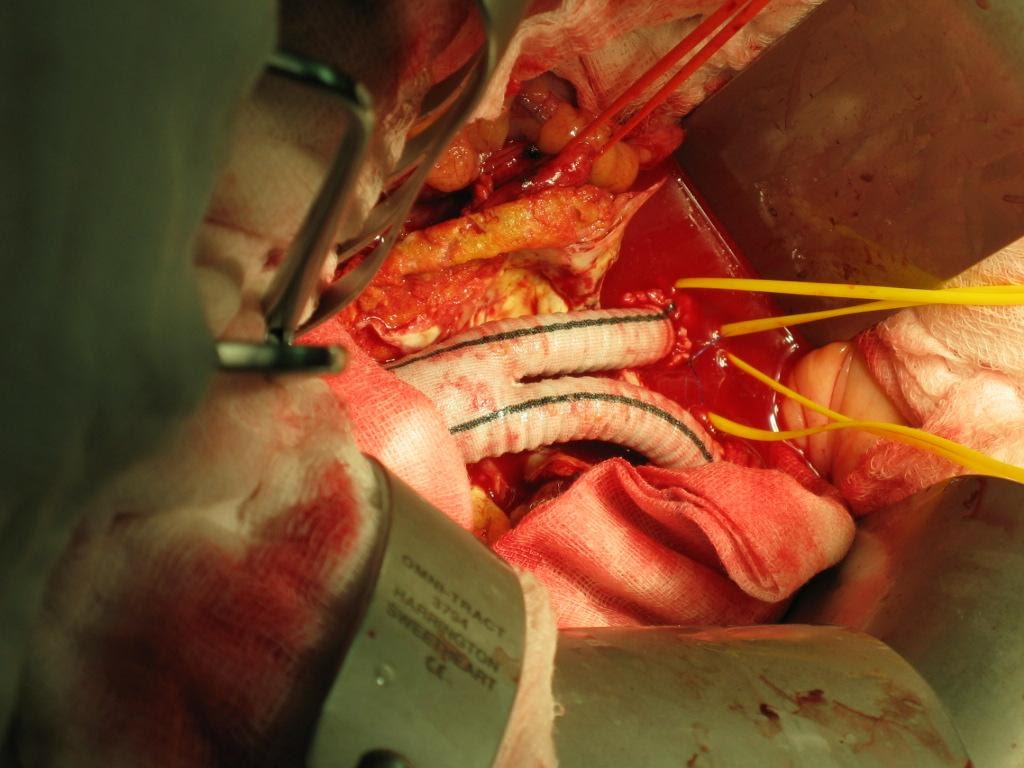

Ever since Juan Parodi put in the first stent graft in an Abdominal Aortic Aneurysm patient during 1990s, the status of open repair and inlay grafting (Figure 5,6) of Abdominal Aortic Aneurysm as gold standard has been challenged.

Figure 6: Intra-op picture of Inlay-graft

Open repair of Abdominal Aortic Aneurysm involves laparotomy, retroperitoneal access, cross clamping of aorta proximal and distal to aneurysm followed by aneurysectomy and inlay grafting. The peri-operative mortality started from 10% and surges with various co-morbid factors. It is not uncommon for a 70 years old AAA patient to present with Hypertension, Diabetes mellitus and Ischemic Heart Disease, as such the peri-operative mortality can be as high as 30-40%. The situation will be worst if patient first presented with leaking or contained ruptured AAA. Prolonged ICU stay post op with ventilator and dialysis support is needed in some cases.